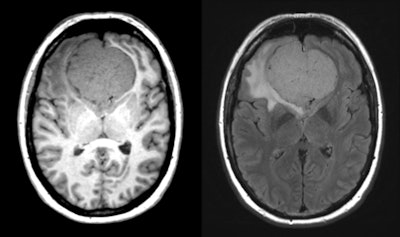

Example of an incidental finding in whole-body MR scan in population-based imaging without contrast enhancement showing an unclear T1-weighted hypointense (right panel), T2-weighted slightly hyperintense (left panel) liver lesion of about 4.5 cm in liver segment VII, which requires further workup. All images copyright Dr. Christopher Schlett.

Example of an incidental finding in whole-body MR scan in population-based imaging without contrast enhancement showing an unclear T1-weighted hypointense (right panel), T2-weighted slightly hyperintense (left panel) liver lesion of about 4.5 cm in liver segment VII, which requires further workup. All images copyright Dr. Christopher Schlett.The survey data included both pre- and postscan survey information for 243 participants. More than half of the participants (57%) noted in the prescan survey that reporting incidental findings in general would be "very important" for them, which decreased to 42% after the scan (p < 0.001); this decrease did not differ whether the participant had an incidental finding reported or not (p = 0.75). A small percentage (3.4%) of patients reported that waiting for the incidental finding report was "very burdening" or "burdening for them. From the participants with reported incidental findings, 9.1% felt that the results were "very burdening," in contrast to 56.8% who classified the results as "very helpful."